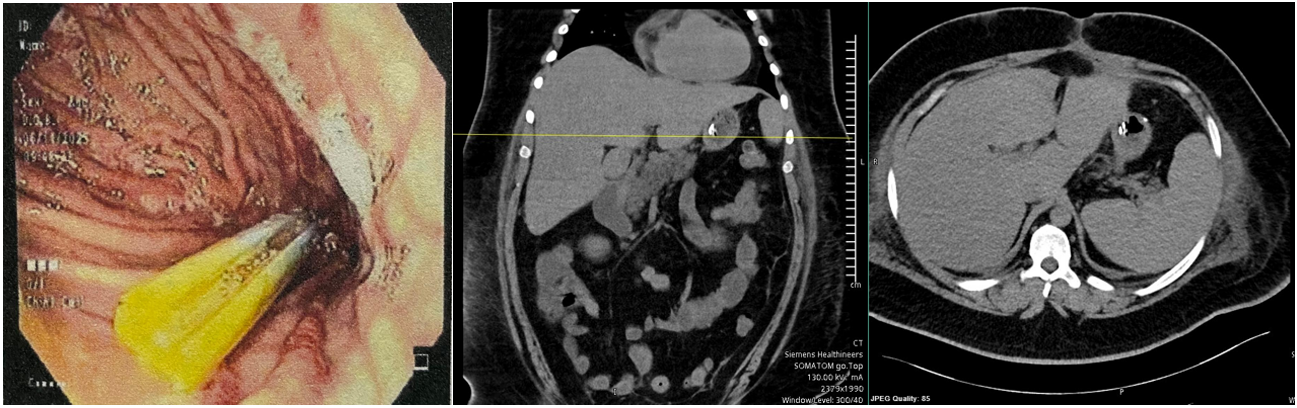

An endoscopic evaluation was performed, revealing a patent gastrojejunal anastomosis without leak (Figure 2). A Blake drain was found to have migrated approximately 10 cm into the gastric lumen (Figure 3). Under direct endoscopic visualization, the drain was withdrawn 12 cm until it was completely outside the stomach, revealing a 6-mm fistulous orifice. The drain was then repositioned and connected to a collection system, and a nasogastric tube was placed as part of conservative management while awaiting fistula closure.

Figure 2: Endoscopic image showing a patent anastomosis with no evidence of leakage.

Figure 3: A. Abdominal CT showing a migrated drain within the gastric cavity, without evidence of collections or leaks. B. Endoscopic image showing a drain migrated into the gastric lumen.